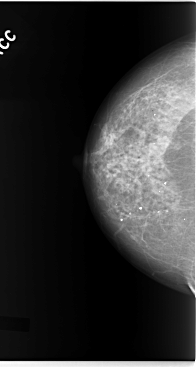

C_0093_1.RIGHT_CC

RIGHT_CC LINES 5872 PIXELS_PER_LINE 3136 BITS_PER_PIXEL 12 RESOLUTION 50 NON_OVERLAY